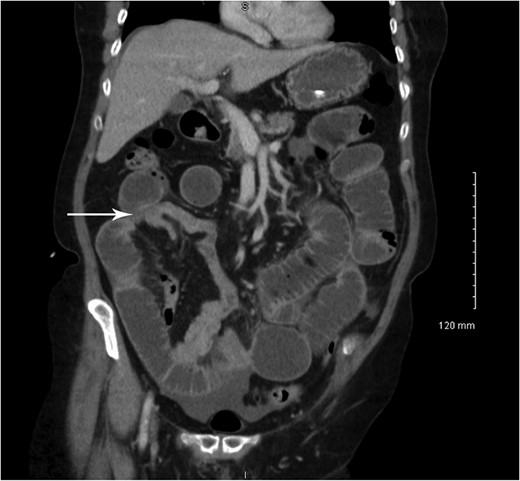

Coronal CT showing small bowel mucosal-enhancing lesion (arrow).